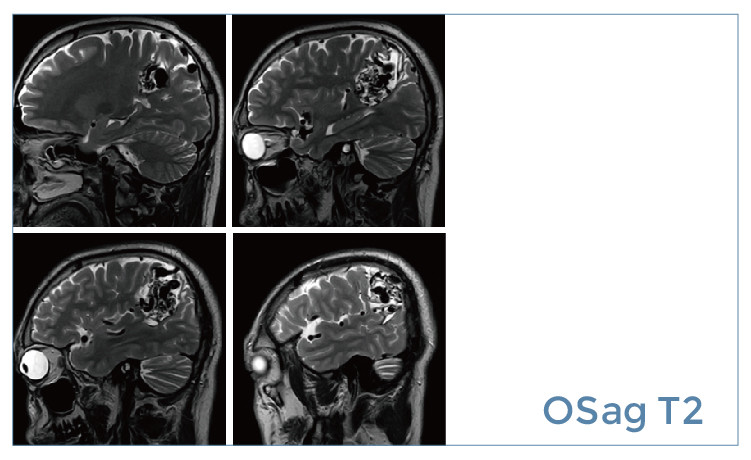

【朗润影像档案】20190531磁共振影像病例结果讨论